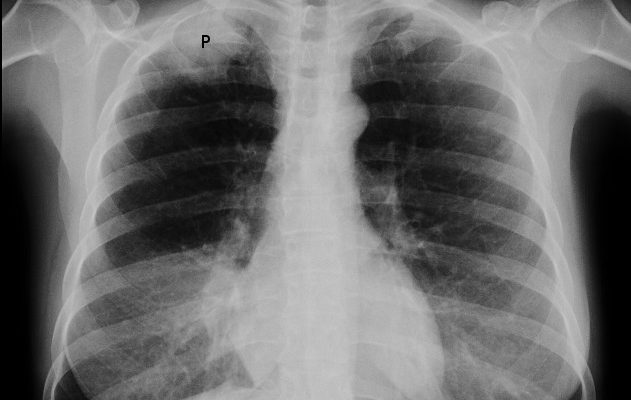

• обзорная рентгенография органов грудной клетки — при опухоли Панкоста на рентгенограмме видны специфические симптомы: затемнение в области верхней борозды, увеличение толщины плевры, разрушение или деформация первых трех ребер, 6 -7 шейных и верхних грудных позвонков;